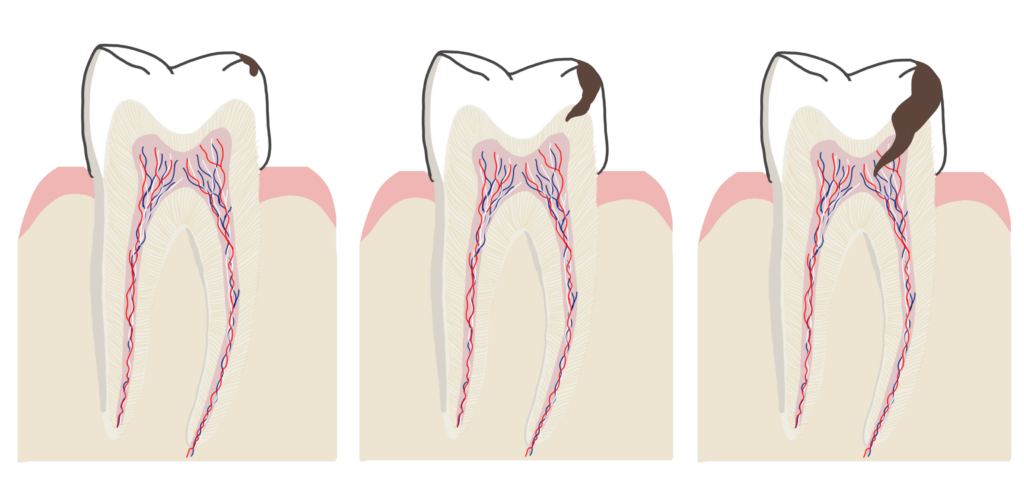

Hi ha diversos tipus de càries segons la profunditat de la lesió, distingim les càries d’esmalt, que són les més superficials i no solen donar cap simptomatologia; les càries de dentina, que són una mica més profundes, arriben a la capa mitja de la dent, i solen donar simptomatologia quan prenem begudes molt fredes o molt calentes i també quan mengem aliments dolços; per últim hi ha les càries que arriben fins a la capa més profunda de la dent, la polpa, aquestes produeixen moltes molèsties i no es pot simplement «empastar» la dent sinó que cal fer un tractament de regeneració polpar o bé una endodòncia.

- ENDODÒNCIA

L’endodòncia és el procediment en el qual es retira el teixit nerviós (nervi) i vascular de la dent, netejant els canals que passen per dintre de cada una de les arrels de la dent. Es desinfecten aquests canals un cop hem retirat tot el teixit i finalment s’omplen amb un material estanc perquè no es puguin tornar a filtrar bactèries i no es faci de nou una infecció.

- REGENERACIÓ DENTINÀRIA I PULPAR

En el cas de càries molt profundes o dents fracturades, si observem que el nervi encara està en bon estat (realitzem proves de vitalitat en diverses sessions), intentem potenciar la regeneració dels teixits afectats per crear una capa protectora i així evitar de treure el nervi.